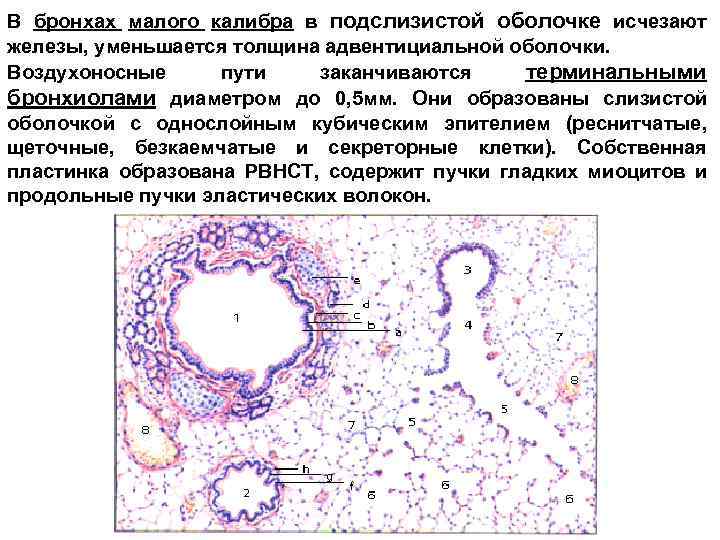

В бронхах малого калибра в подслизистой оболочке исчезают железы, уменьшается толщина адвентициальной оболочки. Воздухоносные пути заканчиваются терминальными бронхиолами диаметром до 0, 5 мм. Они образованы слизистой оболочкой с однослойным кубическим эпителием (реснитчатые, щеточные, безкаемчатые и секреторные клетки). Собственная пластинка образована РВНСТ, содержит пучки гладких миоцитов и продольные пучки эластических волокон.